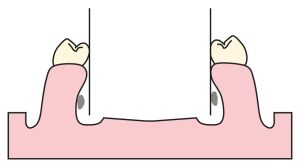

- The mylohyoid ridge, which may become excessively angulated and prominent due to atrophic changes following the extraction of mandibular molars (Figure 7-5),

These anatomical features should be carefully examined during cast surveying, as they may limit or complicate the intended path of insertion. In general, the bone in the premolar region is not as wide as in the molar region, and it is more tapered in the apical area compared to the crest. In such cases, attention must be paid to adapting the buccal flange of the prosthesis according to the undercut area.